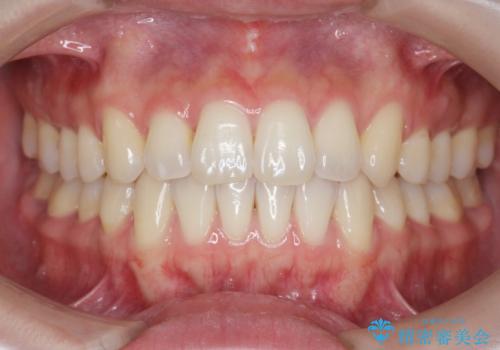

下の歯のがたつき 上より気になる

口元大事です! 見違える矯正!! 乱ぐい歯もあきらめないでください。